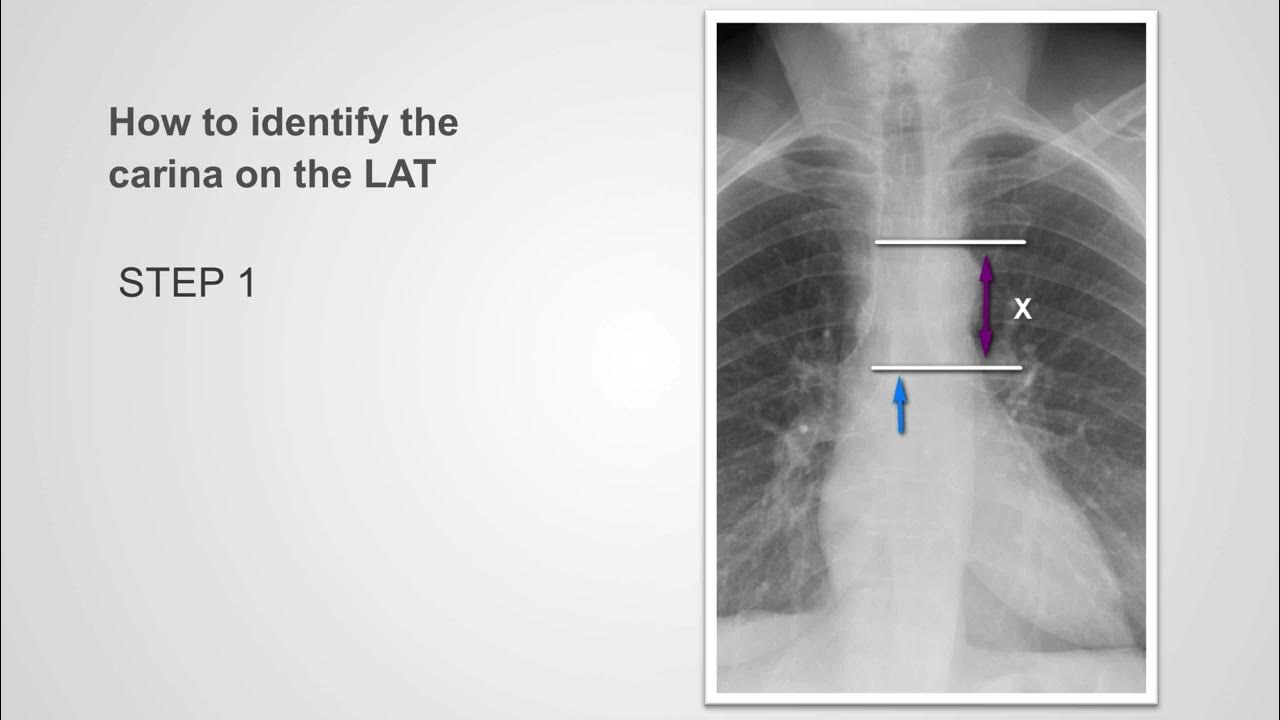

A diagrammatic image of the carina which was prevented at airways and | Download Scientific carina suede women's shoes